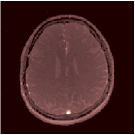

Two sets of experiments were conducted here: first, we used the 2D and 3D acquisition sequences for scanning a healthy volunteer’s brain (real-world acquisitions). Figures 6 and 7 display the parametric maps reconstructed from 2D spiral and radial readouts. We computed the T1, T2 and proton density (PD) maps using baseline reconstruction algorithms ZF, VS, LR, FLOR, AIR-MRF and our proposed LRTV. While baselines use DM either for quantitative inference or also during reconstruction (i.e. AIR-MRF), we further compare the DM-free LRTV’s performance when cascaded to DM, KM and MRFResnet for quantitative inference. For the 3D spiral acquisitions we compared LRTV and its closest competitor VS in Figure 8. Outcomes from other tested algorithm are displayed in the supplementary materials (Figure S5). Since FLOR does not use dimensionality-reduction, our system ran out of memory during 3D reconstruction; hence results are not reported in this case.

The LRTV-DM and LRTV-MRFResnet perform on par, and both outperform all tested baselines for reconstructing T1, T2 and PD maps in all acquisition schemes. This can be observed both visually in Figures 6, 7, 8, S2 and S3, and quantitatively in Table IV across all tested metrics. Other baselines were unable to successfully remove the under-sampling artefacts in TSMIs, and these errors propagated to the parameter inference phase and resulted in inaccurate maps. Temporal-only priors incorporated within LR are shown insufficient to regularise the inverse problem and LR sometimes (e.g. 2D spiral acquisitions) can admit solutions with even stronger artefacts than the model-free ZF baseline. This issue was previously studied for other non-Cartesian MRF readouts that similar to our spiral/radial trajectories, miss to sample the corners of the k-space in all timeframes (see section 2.2.2 and figure 2 in [19]). In the absence of reference for the k-space corners information, the LR iterations despite minimising the objective can converge to solutions with high-frequency artefacts, as visible in the computed maps. This highlights the need for adding an appropriate spatial-domain regularisation. FLOR reduces the LR’s artefacts but this improvement is limited because the suggested nuclear norm penalty does not incorporate an explicit spatial regularisation. Further for reducing artefacts, FLOR can introduce an undesirable bias in the computed T1/T2 maps e.g. see error maps in Figures S2 and S3. The non model-based VS baseline incorporates spatial regularisation and results in spatially smoother maps than ZF and LR, but it is unable to output artefact-free images. Further and consistent with our in-vitro experiment, we observe that VS overestimates the T2 values (e.g. in White and Grey matter regions) in tested 2D acquisitions i.e. the spatial regularisation trades off agains the quantification accuracy. The model-based AIR-MRF adds spatial regularisation through 2D/3D low-pass Gaussian filters however this trades off the sharpness of the computed maps and can increase the errors at the tissue boundaries (we searched Gaussian spreads that keep the blurs and high-frequency artefacts minimal). For our acquisition readouts, Gaussian filters performed better than disk filters of [19] for avoiding strong Gibbs artefacts. On the other hand, the spatiotemporally regularised LRTV greatly improves the TSMI reconstructions i.e. 4 dB enhancement compared to the closest competitor baseline (Table IV). This enables computing accurate and aliased-free multi-parametric inference using DM or the DM-free learning-based alternative MRFResnet as visible in Figures 6, 7, 8, S2 and S3. MRResnet and DM score competitive quantitative inference results i.e. T1 and T2 MAPE less than 5% and 9%, respectively (Table IV). KM also outputs comparably accurate T1 maps, however this shallow learning model despite having a model size larger than MRFResnet, is unable to learn accurate T2/PD quantification and it results in poor estimated maps, consistent with our observations in section VI-C.